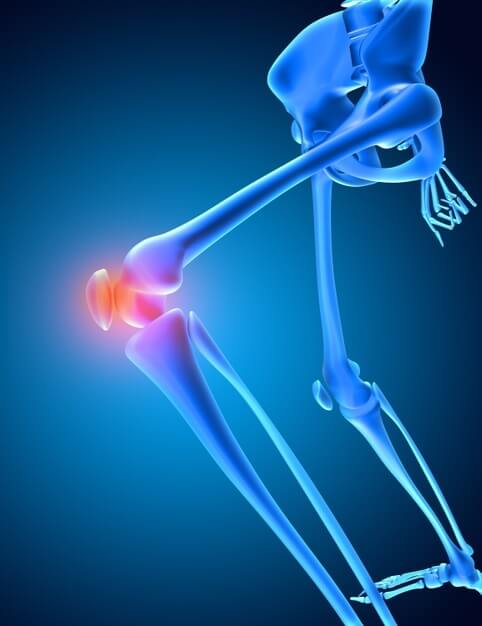

שחיקת מפרקי הברכיים

החלפת מפרק - לא מה שחשבתם

החלפת מפרק - לא מה שחשבתם. מאמר שלישי בסדרת ניתוחים על שולחן הניתוחים

אין לי רצועה צולבת! מאמר שני בסדרת ניתוחים על שולחן הניתוחים